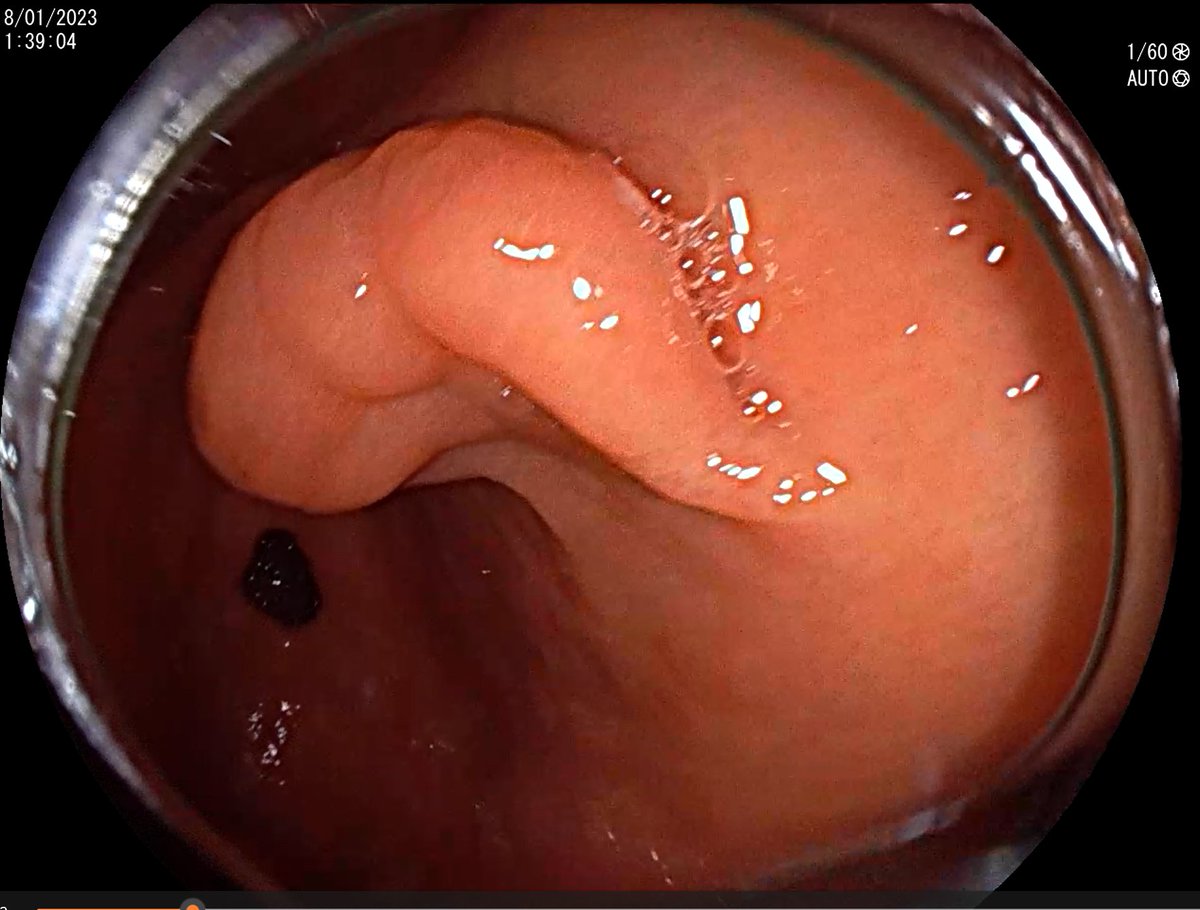

🧐CASO CLÍNICO ENDOSCÓPICO🧐 Mujer 48 años con déficit de B12 y positividad para anticuerpos- Anti FI y Anti ATPasa K/H. Se le realiza gastroscopia para despistaje de Gastritis autoinmune. Vemos esta imagen: